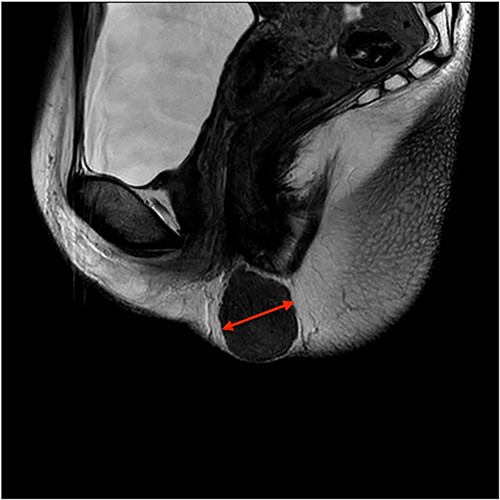

On ultrasound, the lesion was described as a heterogeneous mass with complex internal vascularity, highly suggestive of malignancy. Further workup with magnetic resonance imaging (MRI) demonstrated a 36 × 28 × 23 mm mass at the posterior aspect of the right vulva visible on the coronal (Fig. 1) and axial view (Fig. 2). The lesion was abutting the skin surface but separate from the anus, vagina and urethra, and suspicious for soft-tissue sarcoma.